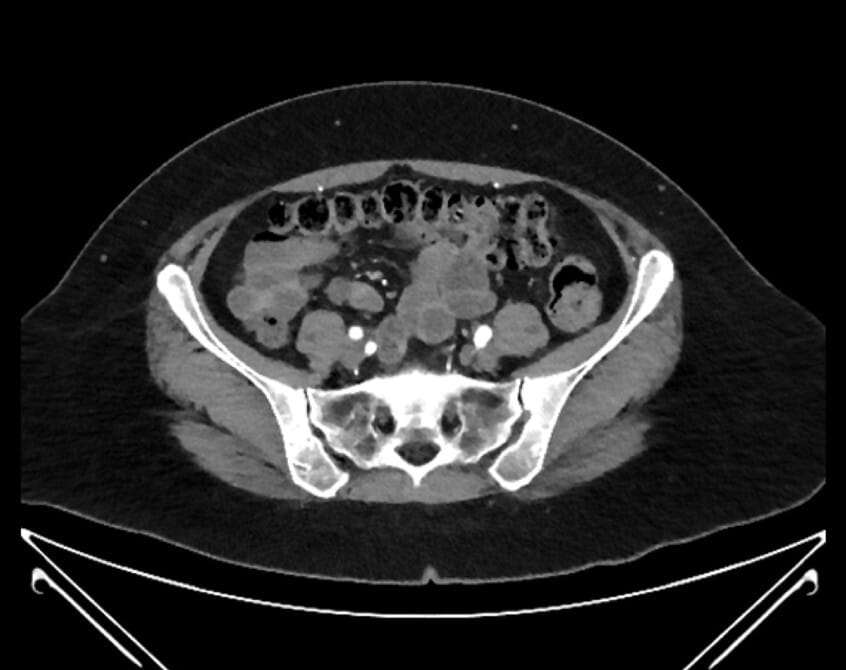

55. right common iliac artery

56. left common iliac vein

57. right common iliac vein

58. left common iliac artery

61. external iliac artery

62. iliolumbar artery

63. internal iliac artery